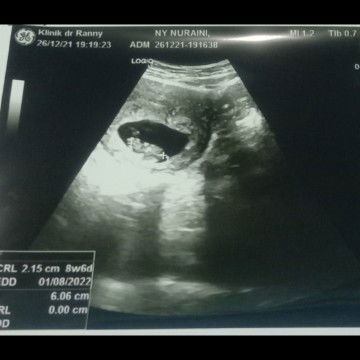

5 Tanda Janin Meninggal Dalam Kandungan

Tahukah Bunda istilah stillbirth? Janin meninggal dalam kandungan setelah usia 5 bulan. Ini tanda-tanda yang perlu diwaspadai https://id.theasianparent.com/bayi-meninggal-dalam-kandungan-usia-9-bulan/web-view/?pinned=post Yuk saling berbagi cerita perjalanan kehamilan Bunda sejauh ini.